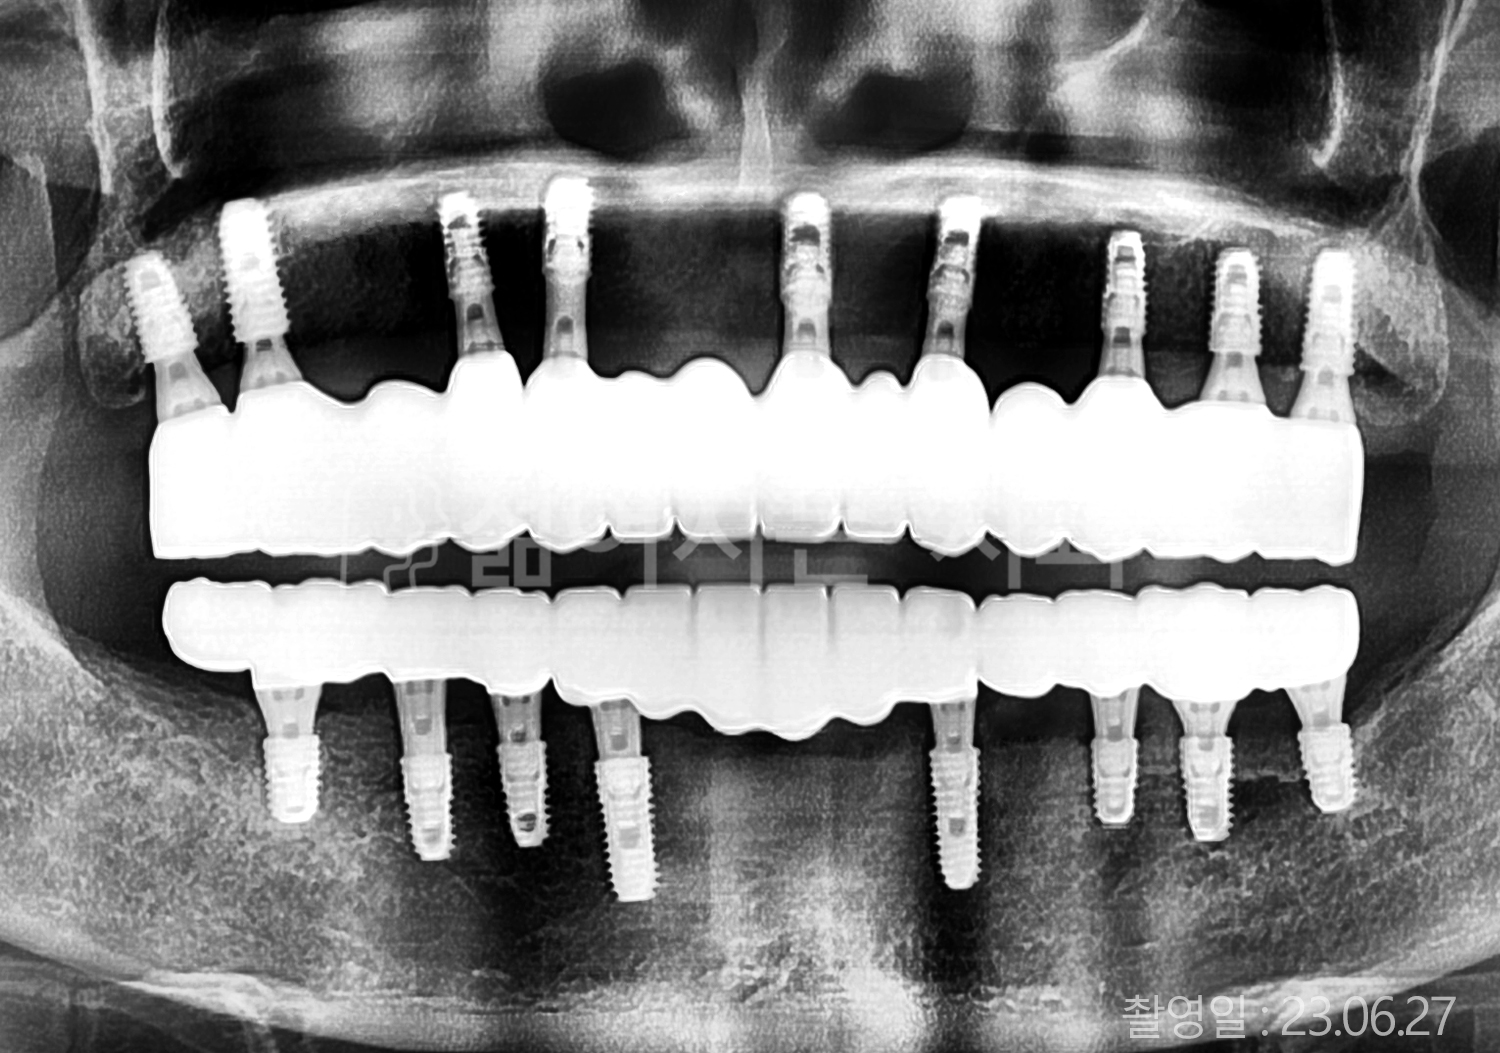

• 60대 고혈압, 고지혈증 전체치아 10개 이상 임플란트

• 70대 전체치아 10개 이상 임플란트

• 60대 전체치아 10개 이상 임플란트

• 50대 전체치아 10개 이상 임플란트

• 50대 고혈압, 고지혈증 전체치아 10개 이상 임플란트

• 60대 고혈압, 당뇨, 고지혈증 전체치아 10개 이상 임플란트

• 80대 고혈압, 당뇨, 골다공증 전체치아 10개 이상 임플란트

• 60대 고혈압 전체치아 10개 이상 임플란트

• 60대 고지혈증 전체치아 10개 이상 임플란트

• 60대 당뇨 전체치아 10개 이상 임플란트